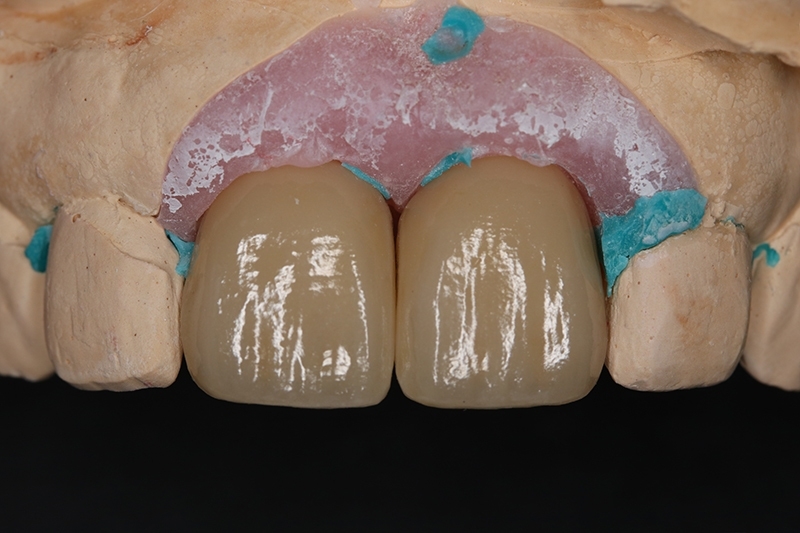

明顯看到水平骨頭缺損範圍

垂直骨頭缺損情況

不可吸收再生膜Cytoplast

修剪合適範圍,並在舌側固定

牙脊增寬術人工骨粉放置使用 cerabone

垂直水平補骨增寬

迷你骨釘Tack固定再生膜及骨粉

迷你骨釘固定再生膜及骨粉